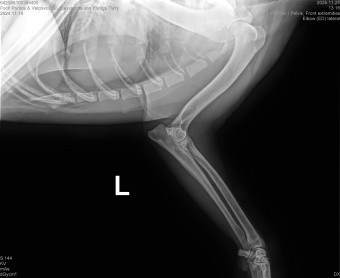

CASSANDRA VON KONIGS-TERRY

( CASSY )

Data nasterii:

14.11.2024

FOCK RODICA si VALCOVICI ION